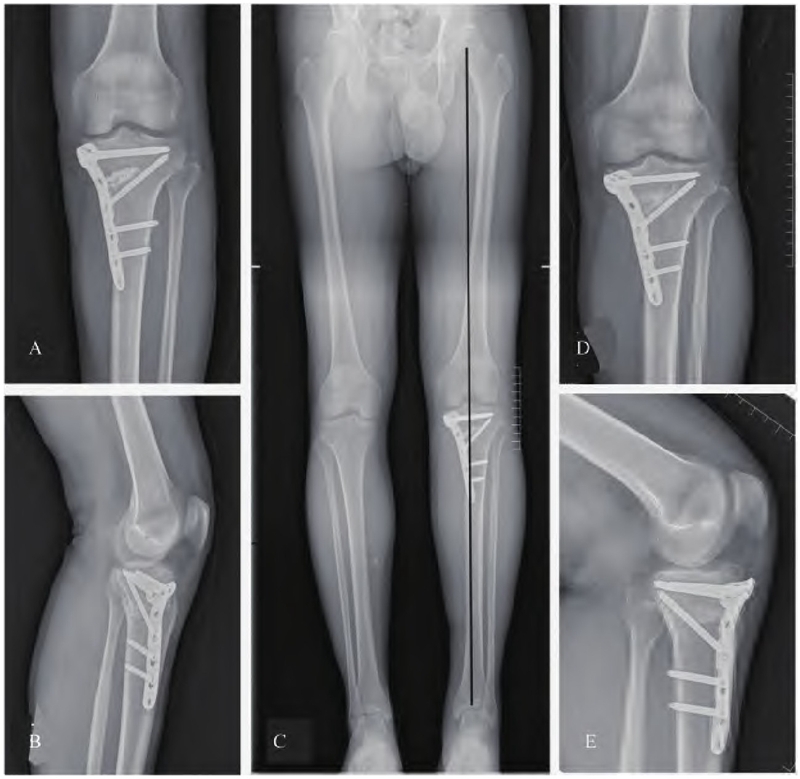

患者术后第一天,开始进行踝关节跖屈和背伸,股四头肌等长收缩。膝关节可进行被动屈曲锻炼,拄拐不负重下地活动。术后第3天行下肢全长X线显示下肢力线满意,胫骨平台内侧畸形纠正满意(图4 A-C)。术后2周,切口愈合良好拆线。术后3个月复查,患者胫骨平台截骨处愈合良好(图4 D-E),患者左膝无明显疼痛,屈曲130°,伸直0°,左足感觉活动功能正常。

图4 术后复查情况